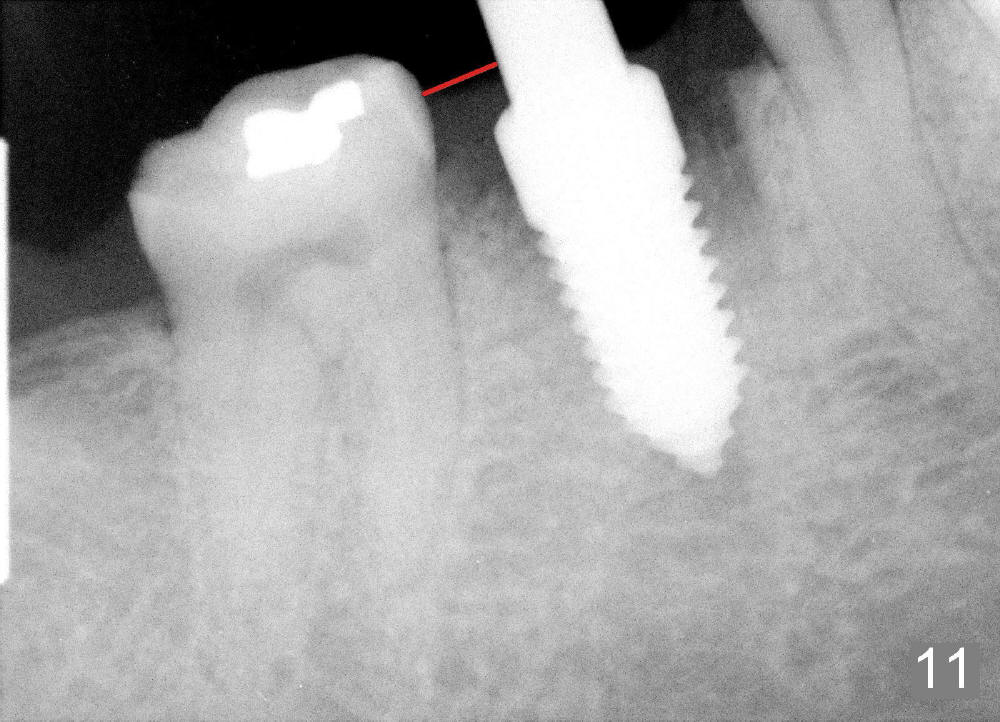

A 38-year-old lady agrees to have implant placement 7 years after loss of the crown of the lower right first molar (Fig.1,2). When the tooth is extracted, the septum is found to be low (Fig.3,4). To confirm it, a PA is taken (Fig.5). To initiate an osteotomy in the septum, it is trans-sectioned with thin osteotomes as shown in Fig.4 insert (black line). A 2 mm pilot drill is placed in the septum (Fig.6: P). The osteotomy is enlarged by 2.5-4.0 mm reamers (Fig.7,8), followed by insertion of 6x17 mm tapered tap at the depth 14 mm (Fig.9). The osteotomy is further enlarged by 4.5 and 5.0 mm reamers. A 6.0x14 mm one piece implant is placed initially. The trajectory is not ideal. A 6.0x14 mm one piece implant is placed initially. The trajectory is not ideal. The implant is removed from the osteotomy partially and reinserted with improved trajectory (Fig.11, compare to Fig.10 (red line)). Primary stability is high. There is not much bone mesiodistally so that the trajectory is easily changed in that direction. After abutment preparation, mixture of autogenous bone (harvested from reamers) and allograft is placed in the residual mesial and distal sockets (Fig.12). To contain the bone graft, an immediate provisional is placed (Fig.13 P). The occlusal plane of the provisional is significantly lower than that of the adjacent teeth to avoid micromovement of the implant. The patient is advised to eat soft food on the left side. Six days postop, the patient returns for prophy. The provisional is removed; the bone graft appears to be incorporating into the socket (Fig.14). After recementation, the provisional remains in place for 3.5 months; PA shows increased bone density in the mesial and distal sockets (Fig.15, compare to Fig.5,11). Due to insurance coverage, the patient defers fabrication of definitive restoration for at least 7 months. The immediate provisional is finally lost 8.5 months postop: the gingiva attaches to the 1-piece implant (Fig.16), while the density of the mesial socket increases (Fig.17 *) with formation of the cortex (lamina dura) coronally (v). Before the provisional (Fig.18 P) is removed for cementation of the definitive restoration, black shadow (*) is noted over the buccal gingiva. It is partially due to buccal placement (Fig.19) and partially due to buccal atrophy over a period of 10.5 months postop. How to prevent buccal placement? Positioning the first pilot drill in the septum buccolingually is a key. Eleven months post crown (Fig.20 C) cementation, the black shadow remains, but there is no tenderness. If the implant threads are immediately underneath the periosteum, there is tenderness.